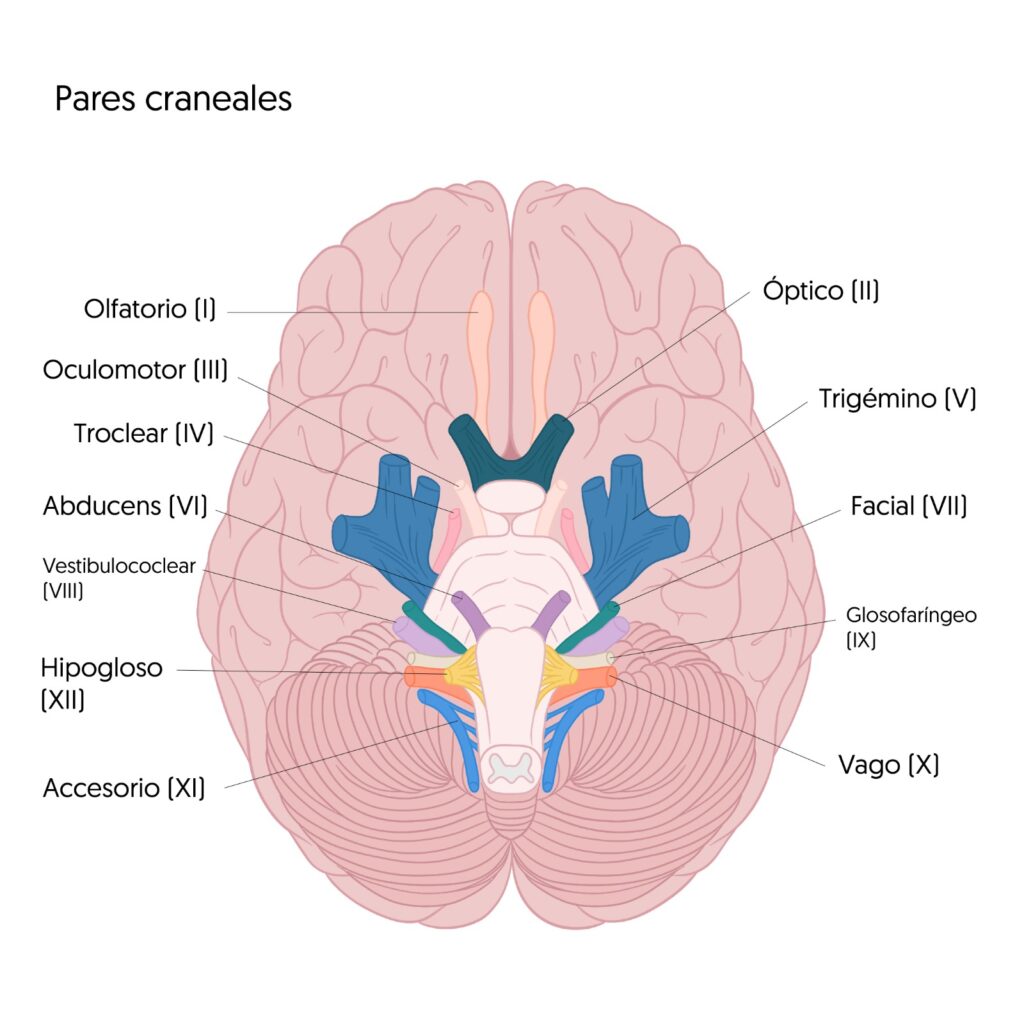

El cerebro humano es un órgano complejo que controla todas nuestras funciones vitales y nos permite interactuar con el mundo que nos rodea. En él, existen 12 pares de nervios conocidos como los pares craneales que desempeñan un papel fundamental en la comunicación entre el cerebro y diferentes partes del cuerpo. Estos, también llamados los 12 apóstoles del cerebro, son responsables de funciones sensoriales y motoras. A continuación, profundizaremos sobre qué son, cómo funcionan y qué importancia tiene cada uno de los 12 pares craneales.

Los nervios craneales son una colección de 12 pares de nervios que se originan en la base del cerebro y se extienden hacia diferentes regiones de la cabeza, el cuello y algunas partes del cuerpo. Estos nervios desempeñan un papel crucial en la transmisión de señales sensoriales y motoras entre el cerebro y diversas estructuras, como por ejemplo los músculos y también órganos sensoriales.

Así, cada par tiene una función específica y única, ya sea en el control de los movimientos oculares, el sentido del olfato, la visión, audición, gusto, sensibilidad facial, función del habla, deglución y otras funciones vitales. Por ello, son fundamentales para el adecuado funcionamiento del sistema nervioso (Sonne et al., 2022).

En este apartado, explicaremos cuáles son los 12 pares craneales, clasificándolos en base a su rol. Esta manera de subdividirlos proporciona un marco organizativo esencial para comprender sus funciones y relaciones anatómicas. En este sentido, podemos dividirlos en: sensoriales, motores y mixtos.

- Nervio Olfatorio (I): Responsable del sentido del olfato, transmitiendo información sobre los olores desde la nariz hasta el cerebro.

- Nervio Óptico (II): Se encarga de la visión, transmitiendo la información visual desde la retina hasta el cerebro para su procesamiento.

- Nervio Vestibulococlear (VIII): Transmite la información relacionada con la audición y el equilibrio desde el oído interno hasta el cerebro.

- Nervio Oculomotor (III): Controla los movimientos de los músculos del ojo, como los movimientos de elevación, descenso y rotación del globo ocular.

- Nervio Troclear (IV): Es responsable del movimiento del músculo oblicuo superior del ojo, que ayuda en la rotación y el movimiento de los ojos.

- Nervio Abducens (VI): Regula el movimiento del músculo recto lateral del ojo, que se encarga de la abducción o alejamiento del ojo del eje central.

- Nervio Accesorio (XI): Controla los músculos del cuello y los hombros, participando en los movimientos de la cabeza y hombros.

- Nervio Hipogloso (XII): Relacionado a los músculos de la lengua, desempeña un papel fundamental en la función del habla y la deglución.

- Nervio Trigémino (V): Este nervio tiene tres divisiones principales. Además, es responsable de la sensibilidad facial, incluyendo la piel, los músculos y las estructuras de la boca y la mandíbula. También controla los músculos de la masticación.

- Nervio Facial (VII): Controla los músculos de la expresión facial y también está involucrado en el sentido del gusto en dos tercios anteriores de la lengua.

- Nervio Glosofaríngeo (IX): Está involucrado en la sensibilidad y el gusto en el tercio posterior de la lengua, así como en la función de la deglución.

- Nervio Vago (X): Es responsable de la inervación parasimpática de varios órganos en el tórax y el abdomen, además de estar involucrado en la fonación, la deglución y la función del corazón.